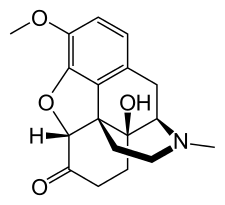

Several semi-synthetic opioids were developed in Germany in the 1910s. The first, oxymorphone, was synthesized from thebaine, an opioid alkaloid in opium poppies, in 1914.[228] Next, Martin Freund and Edmund Speyer developed oxycodone, also from thebaine, at the University of Frankfurt in 1916.[229] In 1920, hydrocodone was prepared by Carl Mannich and Helene Löwenheim, deriving it from codeine. In 1924, hydromorphone was synthesized by adding hydrogen to morphine. Etorphine was synthesized in 1960, from the oripavine in opium poppy straw. Buprenorphine was discovered in 1972.[228]

- Semi-synthetic opioids: created from either the natural opiates or morphine esters, such as hydromorphone, hydrocodone, oxycodone, oxymorphone, ethylmorphine and buprenorphine;

Semi-synthetic alkaloid derivatives

- Hydrocodone